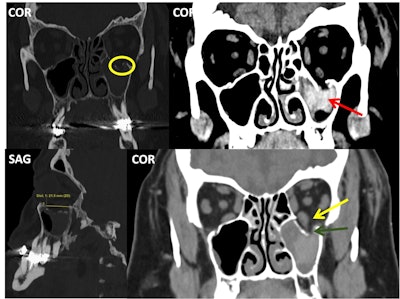

The images on the left side of the white vertical bar show a bilateral, simple, and nondisplaced nasal fracture. The nasofrontal suture (orange arrows), nasal septum (green arrow), and anterior nasal spine (yellow circles) remain intact, while the fracture line crosses the left nasomaxillary suture (red arrows). On the other hand, the image on the right contains a bilateral, comminuted, and displaced nasoseptal fracture (red circle), in which the nasal septum is also involved (red arrow).

Pure and simple blow-out left orbital fracture; the orbital rim and internal orbital buttress remain unaltered. Over half of the orbital floor is involved (measurement in the lower left image), and the fracture line crosses the infraorbital canal (yellow circle). The left inferior rectus muscle (yellow arrow) looks asymmetrical when compared to the contralateral one and appears to be “tractioned” with accompanying intraorbital fibrofatty tissue into the left maxillary sinus (dark green arrow); the sinus also has hyperdense content compatible with a hematoma (red arrow).